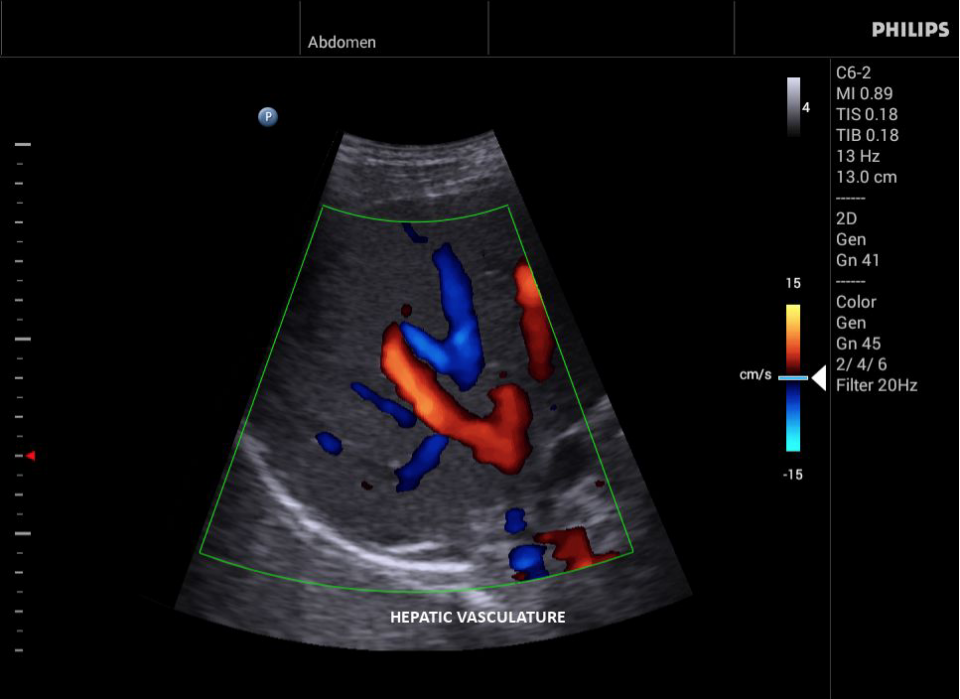

Philips InnoSight

Philips InnoSight увеличивает возможности сканирования во множестве мест оказания медицинских услуг. Благодаря данному УЗИ аппарату врачи могут не сомневаться в быстром выполнении обычных ультразвуковых сканирований во врачебном кабинете, клинике или больнице.

InnoSight позволяет перенести ультразвуковую диагностику непосредственно туда, где пациенту оказывается медицинская помощь, что повышает мобильность врачей. Этот компактный и легкий ультразвуковой аппарат позволяет чаще использовать возможности ультразвуковой диагностики и предоставляет широкий набор технологий для проведения углубленных исследований — программные пакеты для специализированного анализа, функции аннотирования и наборы готовых настроек для различных типов тканей.

Эргономичная система с высококачественными широкополосными датчиками Philips помогает повысить клиническую надежность результатов исследования и уровень оказания медицинских услуг. Аппарат можно перемещать вручную или с помощью тележки.

• Исследования сосудов;

• Цветное допплеровское картирование

• Конвексный УЗИ датчик Philips С6-2

• Конвексный УЗИ датчик Philips C5-2